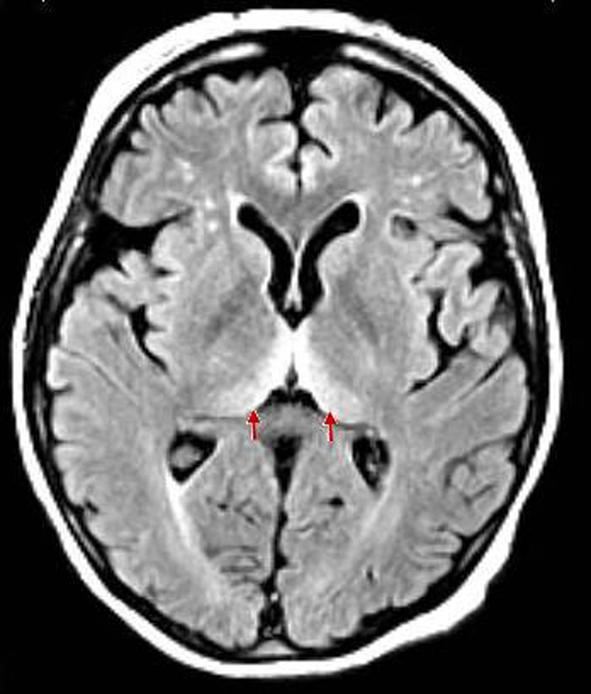

pulvinar sign - bilateral FLAIR hyperintensities of pulvinar thalamic nuclei

can be seen in CJD, Fabry, status, ADEM

hockey stick sign

bilateral hyperintensity of pulvinar nuclei and medial thalamus

can be seen in CJD or Wernicke’s